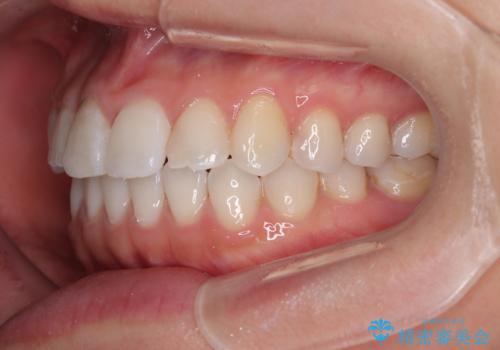

捻れた前歯を楽して改善 ワイヤー装置での非抜歯矯正

- 上下前歯のデコボコを気にして来院された患者様です。

ワイヤー矯正でもマウスピース矯正でも可能でしたが、短期間で、自身の手を煩わせることなく治療を行いたいとのことで、ワイヤー装置にて矯正治療を行うこととしました。

ご本人の中では2年近くかかるものと思っていたそうですが、1年で治療を終えることができ、大変満足していらっしゃいました。